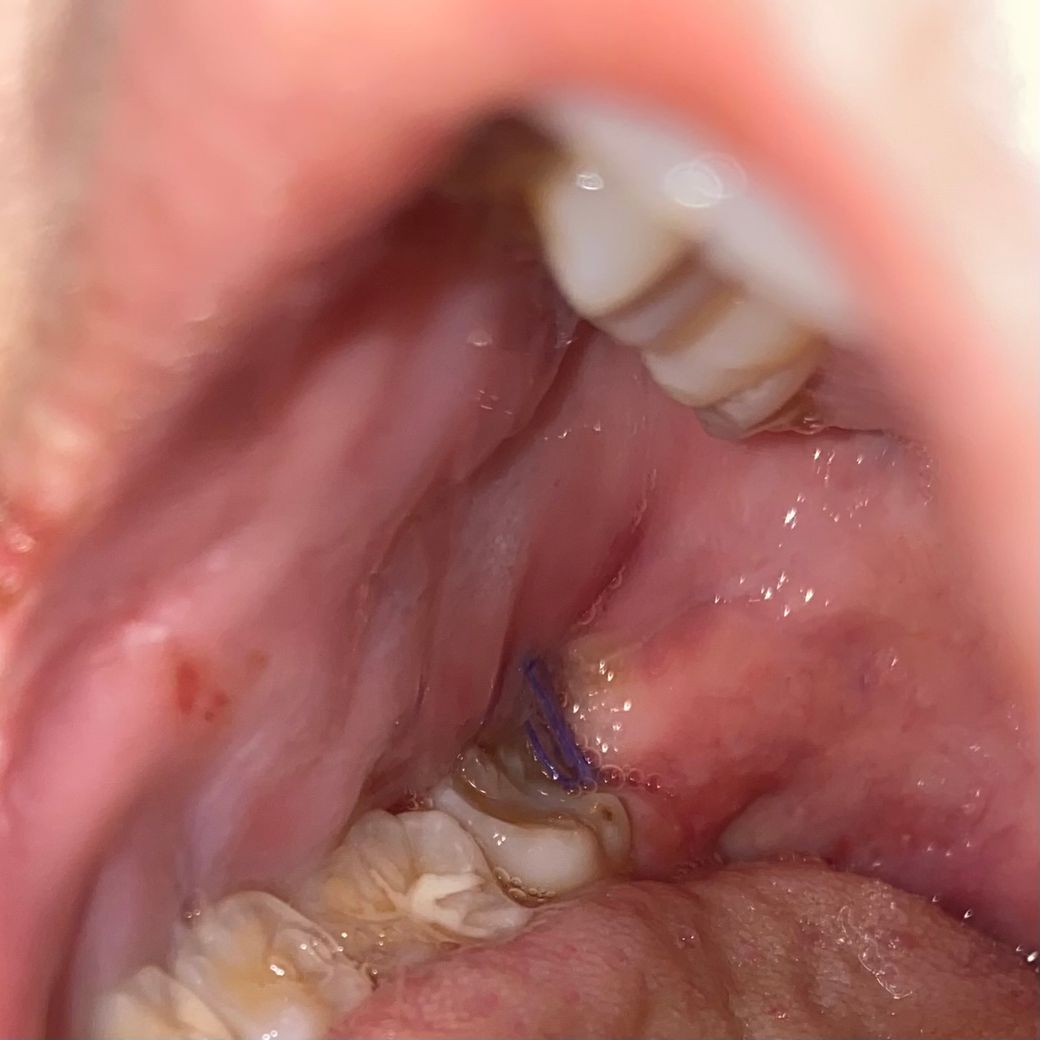

5월 3일날 오른쪽 매복 사랑니를 대학병원가서 상담받다가 신경이랑 너무 가깝다고 ct촬영하고 피검사까지 하고 2시간 정도 수술했는데 뼈를 정말 많이 깍아서 조금씩 뽑았다 하더라구요 1일째 참을만 한 고통에 피는 6시간만에 지혈됐습니다 지금 3일째 차가운 죽을 먹는데 먹고싶은거 고기나 국물류 같이 다 먹고있습니다 그런데 지금 통증은 없는데 피가 조금씩 나와서 침을 한번 씩 삼킬 때 마다 피맛이 느껴지구요 붓기가 터질듯이 엄청 심했다가 지금 조금씩 빠지고있습니다 피는 다시 거즈를 물고있으면 될까요.. 정확하게 호전이 잘 되고 있는건지, 그리고 치과가서 소독은 꼭 해야되는지 궁금합니다.

현재 사진상 발치부위에 문제가 있지 않으며, 발치후 1-2주간은 통증이 나타나는 것은 정상적인 반응입니다. 소독용 헥사메딘 가글로 관리를하고, 통증이 심한 경우 소염진통제 복용을 권합니다.

안녕하세요 치과의사 김철진입니다. 사진상으로 보면 치유는 잘되고 잇는거 같습니다. 자극이 가지 않도록만 주의 하시면 크게 문제가 되진 않을것같습니다.

말씀하시는 증상과 사진으로 판단 했을때는 정상적인 치유과정 중에 있는 것으로 보입니다.